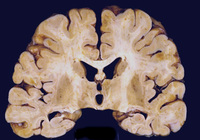

Corte coronal do cérebro de paciente com vírus da imunodeficiência humana (HIV) aos 30 anos. Ele tinha encefalite por HIV subaguda envolvendo tanto a substância branca quanto a substância cinzenta de forma difusa. Os ventrículos estavam aumentados refletindo substância branca e perda cortical

Do acervo pessoal de Robert E. Schmidt; usado com permissão

Veja esta imagem em contexto nas seguintes seções: